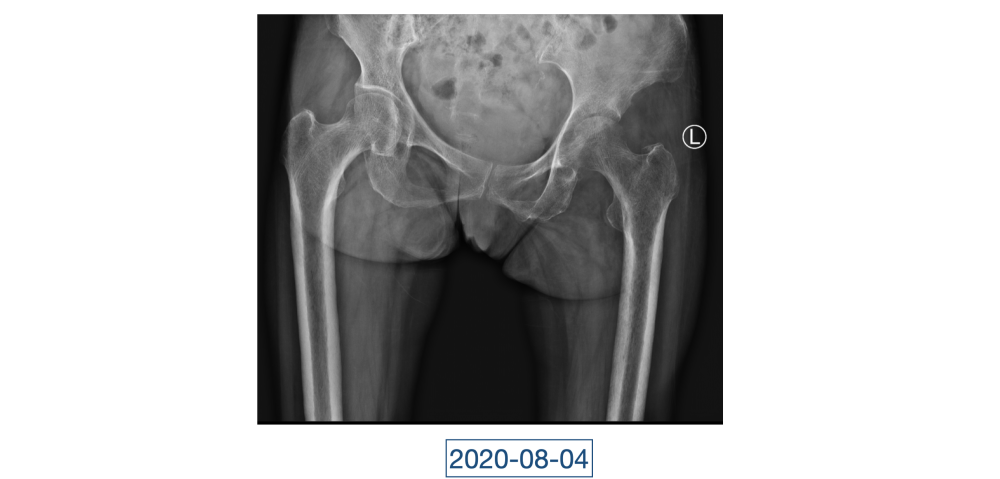

一直到了四月,因为髋关节疼痛的原因,她又来到红会医院关节病医院。李辉见到的黄大娘是坐着轮椅的,家里人说她已经到了卧床不起的地步,原本近107斤的人只用了3个月时间就瘦到了34斤。“这是患上了什么大病,才能让人变成这个样子?”看着憔悴不堪,可以用皮包骨头来形容的黄大娘,李辉心里一沉,担心起来。

全身上下11处骨关节被破坏!密密麻麻的诊断看得李辉毫无思绪,这么久都查不出来的病因能让他查出来吗?一时间,他也说不出话。看着黄大娘深深凹陷的双眼,浑身上下几乎看不见肉,就像罩着一层饥饿的青黄色的薄皮。过了好一会儿,他叹了口气,说:“先住下吧,用药把关节疼痛缓解一下,再想办法。”

经过科室讨论、会诊,李辉也查阅了很多资料,按照黄大娘的症状,他跟之前的接诊医生一样,觉得应该是骨关节感染。可之前的穿刺、培养各种检查也做过,为什么没有找到致病菌?李辉想,或许是检查中出现了问题,没有查对地方。于是他决定,在B超引导下骨穿刺,通过最新技术精准定位病灶,只有这样也许才能抓到真正的“罪犯”。

在黄大娘入院第四天,李辉将她推入检查室,结果很快出来了,为烟曲霉菌感染。这个结果验证了李辉的想法,也解释了此前抗感染药物为何一直不奏效。“找到元凶就好办了,对症用药就可以。真菌感染本来治疗时间就很长,骨科类感染灶治疗时间更长,用了5个月的时间,终于治好了。”

近日随访得知黄大娘身体好转,李辉脸上的笑容掩饰不住,他说,据查阅文献,11处感染灶,这是全世界感染灶最多的骨关节感染,但现在,这罕见、复杂的病已经被治愈。